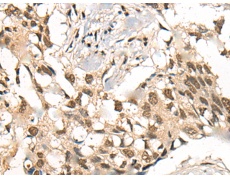

IHC positive control: |

Human esophagus cancer and Human lung cancer |

IHC Recommend dilution: |

20-100 |